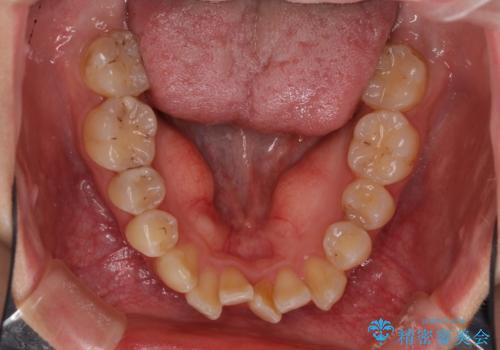

- 中学生の時に矯正治療をしたものの、後戻りを気にして来院された患者様です。

骨格的に下顎が右側に変位しているため、左右の咬み合わせを理想的なものに改善することはできませんが、インビザラインにて歯列を整えることとしました。

骨格的なズレによる左右差は改善できませんでしたが、上下の正中を極力合わせるようにすることができました。